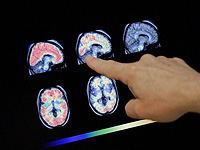

Донор спермы с генной мутацией, радикально повышающей риск развития рака, стал отцом 200 детей по всей Европе. Это выяснилось в ходе масштабного расследования, проведенного крупными вещателями, включая CBS News, BBC News.